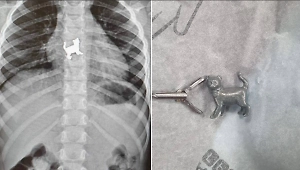

Врачи Подольской областной клинической больницы спасли 64-летнего мужчину, который пожаловался на боли в пищеводе. Оказалось, что во время еды у него открепился металлический зубной мост и пациент его проглотил.

"При визуальном обследовании верхних отделов желудочно-кишечного тракта повреждений слизистой пищевода не было выявлено, а при осмотре желудка был обнаружен проглоченный металлический зубной мост. Мы извлекли зубной протез с помощью специальной петли. С момента обращения пациента до извлечения инородного тела прошло около 30 минут", — сообщил врач-эндоскопист отделения эндоскопии Подольской больницы Виктор Чернов.

Подольские врачи спасли пациента, проглотившего зубной мост. Фото © Минздрав Московской области